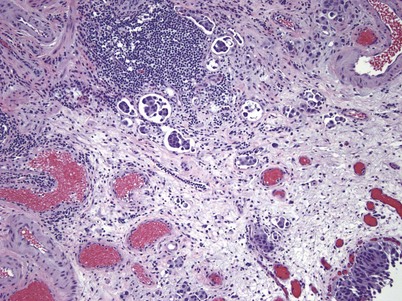

There are key genetic and phenotypic changes that occur in cancer cells, thus providing the ability to invade the underlying stroma. Invasive urothelial carcinoma is divided into two groups: lamina propria and deep muscle invasion. Lamina propria invasive tumors are high-grade cancers that can be in clusters or in single cells, with single-cell invasion having a worse prognosis (Fig. 80–11). Rarely, low-grade cancers can invade the lamina propria. Vascular invasion can occur within the lamina propria because of the large vascular network within this tissue layer; however, it is frequently overcalled because of retraction artifact around tumor nests. There is a subdivision of lamina propria invasion into T1a (invasion above muscularis mucosa) and T1b (invasion below the muscularis mucosa). This subject will be dealt with more extensively in the Staging section.

The key phenotypic change that occurs in urothelial cancer that is destined to metastasize is the ability to invade the angiolymphatic system, which is seen in approximately 25% of invasive urothelial carcinoma (Fig. 80–13) (Kunju et al, 2008). Angiolymphatic invasion is a poor prognostic sign with a 40% risk of nodal disease and is an independent predictor of overall and cancer specific survival (Abdel-Latif et al, 2004; Lotan et al, 2005). A transurethral resection of the bladder tumor can detect angiolymphatic invasion that is subsequently found in the radical cystectomy specimen 65% of the time. It is critical to use CD-31 and CD-34 monoclonal antibodies with immunohistochemistry to accurately identify the blood vessels in contrast to tumor retraction artifacts (Lotan et al, 2005; Kunju et al, 2008).